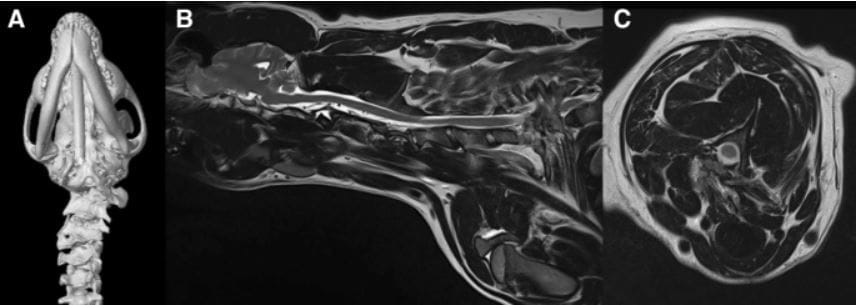

Klippel-Feil-like Syndrome. a Ventral view of a 3D CT-reconstruction of the cervical spine and skull showing complete absence of the left transverse process of the atlas and an asymmetric fusion of C3 and C4 in case 4. b Parasagittal T2W magnetic resonance sequence of the cervical spinal cord showing fusion of C2, C3 and C4. c Axial angular malformations and soft tissues contortion